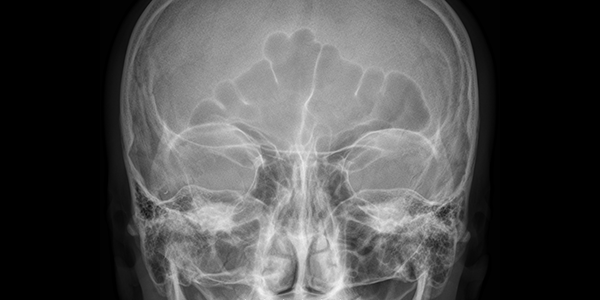

Рентгенография орбит в 1-й проекции (со снимком)

Рентгенография орбит проводится с целью исследования костей глазницы.

В этой области явно или скрыто могут протекать воспалительные, дегенеративные, злокачественные и иные процессы, и при появлении подозрительных признаков показан именно этот вид диагностики.